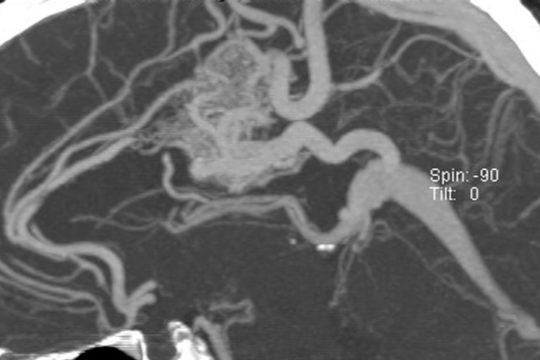

It is not clear why AVM’s form, but some researchers believe that these tangles of vessels are present from birth (a congenital disorder). Several rare genetic diseases are associated with AVM’s. AVM’s classically appear as a complex tangle of abnormal thinly-walled vessels called a “nidus”. A distinguishing feature is that they occur anywhere within the brain or spinal cord. AVM’s are rare, occurring in about 0.2% of the population (200 cases per 100,000 people).

While a CT (computed tomography) or MRI (magnetic resonance imaging) test of either the brain or spinal cord will typically first detect these lesions, catheter-based diagnostic (cerebral or spinal) angiography is essential to fully understand and characterize the AVM. This evaluation allows your doctor to determine your future risk of symptoms and your treatment options. Treatment of an AVM depends on whether symptoms are present or not, how large the lesion is, where it is located and a host of other features only determined by the diagnostic (cerebral or spinal) angiogram.